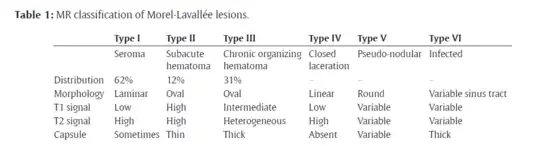

The Mellado-Bencardino classification can be used to describe a Morel-Lavallée lesion based on its MRI.[5] The classification categorizes the lesions into types.[8] The classification has six stages listed as Type I to Type VI.[5] The types do not align with specific treatments or outcomes.[4][8] The stages are based on multiple factors that can be observed on the lesion's MRI.[5] These factors include the following: the shape of the lesion, specific MRI features, and whether a capsule is present.[5][8]